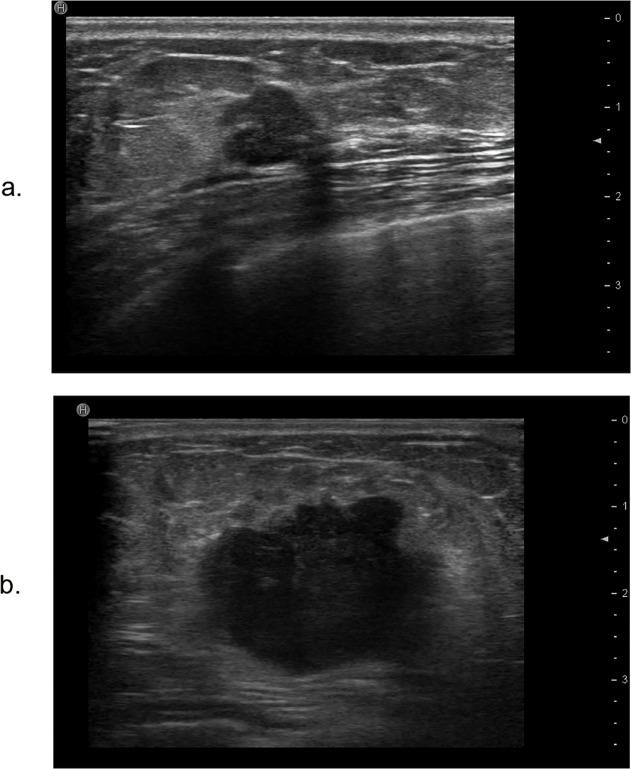

Of the 62 TNBC cases, 42 (67.7%) exhibited the basal-like phenotype and 20 (32.3%) exhibited the normal-like phenotype based on the immunohistochemical CK5/6 and EGFR markers. Of all the tumors, 90.3% were invasive carcinomas. The basal-like tumors were significantly associated with a maximum diameter on ultrasound of more than 20 mm (36, 85.7%) (P = 0.0014). The normal-like tumors usually exhibited lateral shadows (15, 75%) (P = 0.0115) as well as microlobulated margins (12, 60%) (P = 0.0204) compared to the basal-like subtype. Other ultrasound features showed no significant differences between the two groups.

Although ultrasound cannot yet be used to differentiate between the basal-like subtype and normal-like subtype of TNBC, ultrasound can be used to provide some useful information to the clinicians.